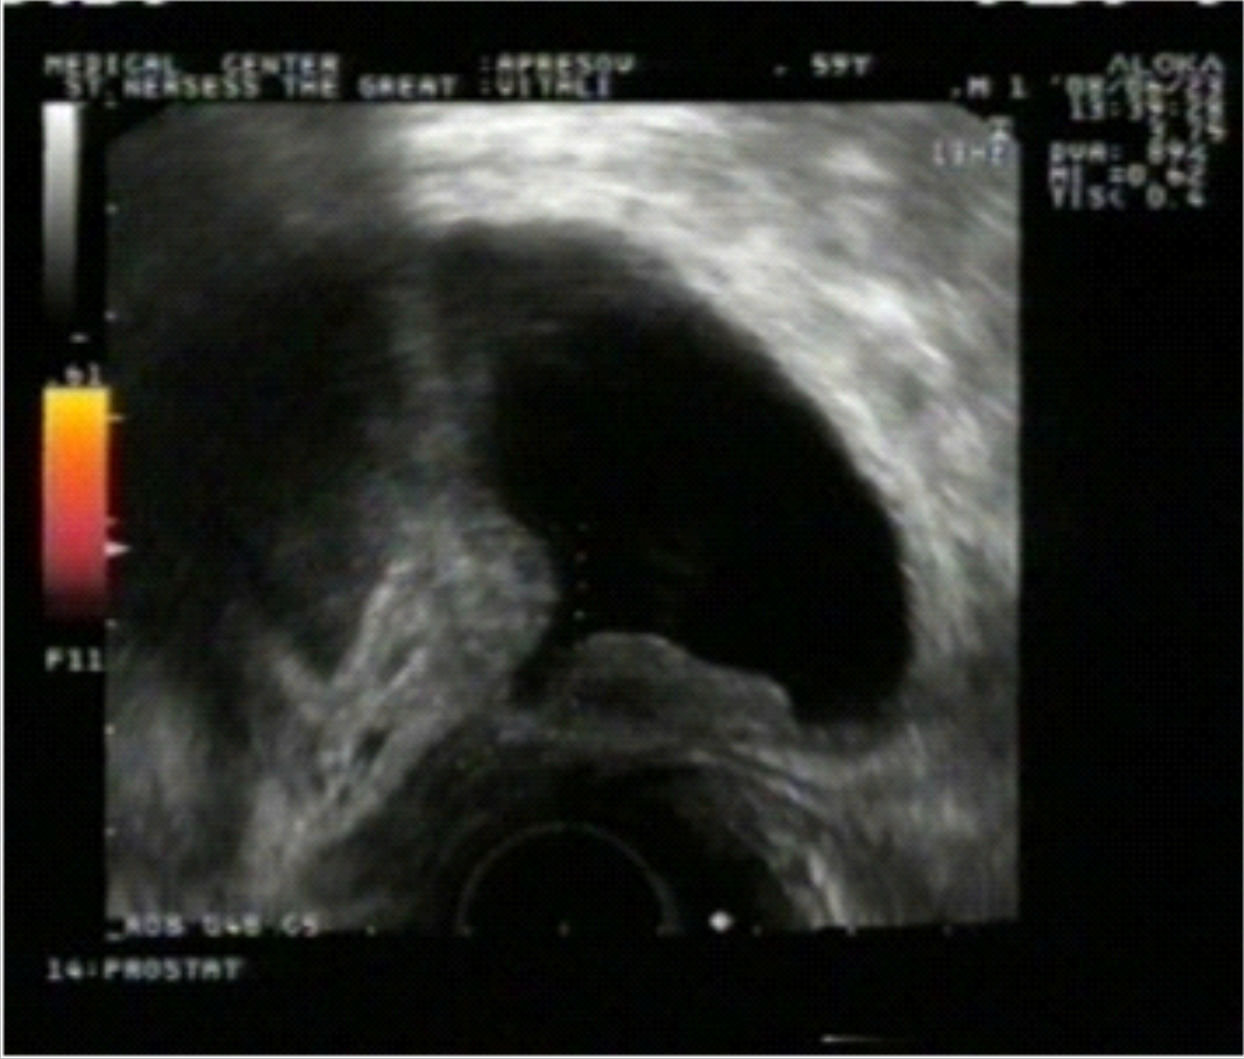

Նկ. 3 Նկ. 4

Նկար 3-ում պատկերված է միզապարկ-միզուկային բերանակցման հատվածի մեկ այլ դեպք, որտեղ չկան տեղային ռեցիդիվի նշաններ: Նույն դեպքը էներգետիկ դոպպլեր ռեժիմով (նկ. 4) դիտելիս չի տալիս հիպերվասկուլյար հյուսվածքային նշաններ: